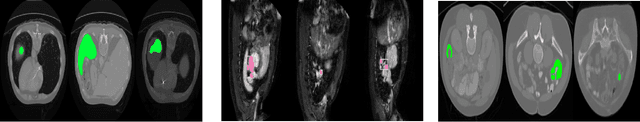

Abstract:Today, deep convolutional neural networks (CNNs) have demonstrated state-of-the-art performance for medical image segmentation, on various imaging modalities and tasks. Despite early success, segmentation networks may still generate anatomically aberrant segmentations, with holes or inaccuracies near the object boundaries. To enforce anatomical plausibility, recent research studies have focused on incorporating prior knowledge such as object shape or boundary, as constraints in the loss function. Prior integrated could be low-level referring to reformulated representations extracted from the ground-truth segmentations, or high-level representing external medical information such as the organ's shape or size. Over the past few years, prior-based losses exhibited a rising interest in the research field since they allow integration of expert knowledge while still being architecture-agnostic. However, given the diversity of prior-based losses on different medical imaging challenges and tasks, it has become hard to identify what loss works best for which dataset. In this paper, we establish a benchmark of recent prior-based losses for medical image segmentation. The main objective is to provide intuition onto which losses to choose given a particular task or dataset. To this end, four low-level and high-level prior-based losses are selected. The considered losses are validated on 8 different datasets from a variety of medical image segmentation challenges including the Decathlon, the ISLES and the WMH challenge. Results show that whereas low-level prior-based losses can guarantee an increase in performance over the Dice loss baseline regardless of the dataset characteristics, high-level prior-based losses can increase anatomical plausibility as per data characteristics.